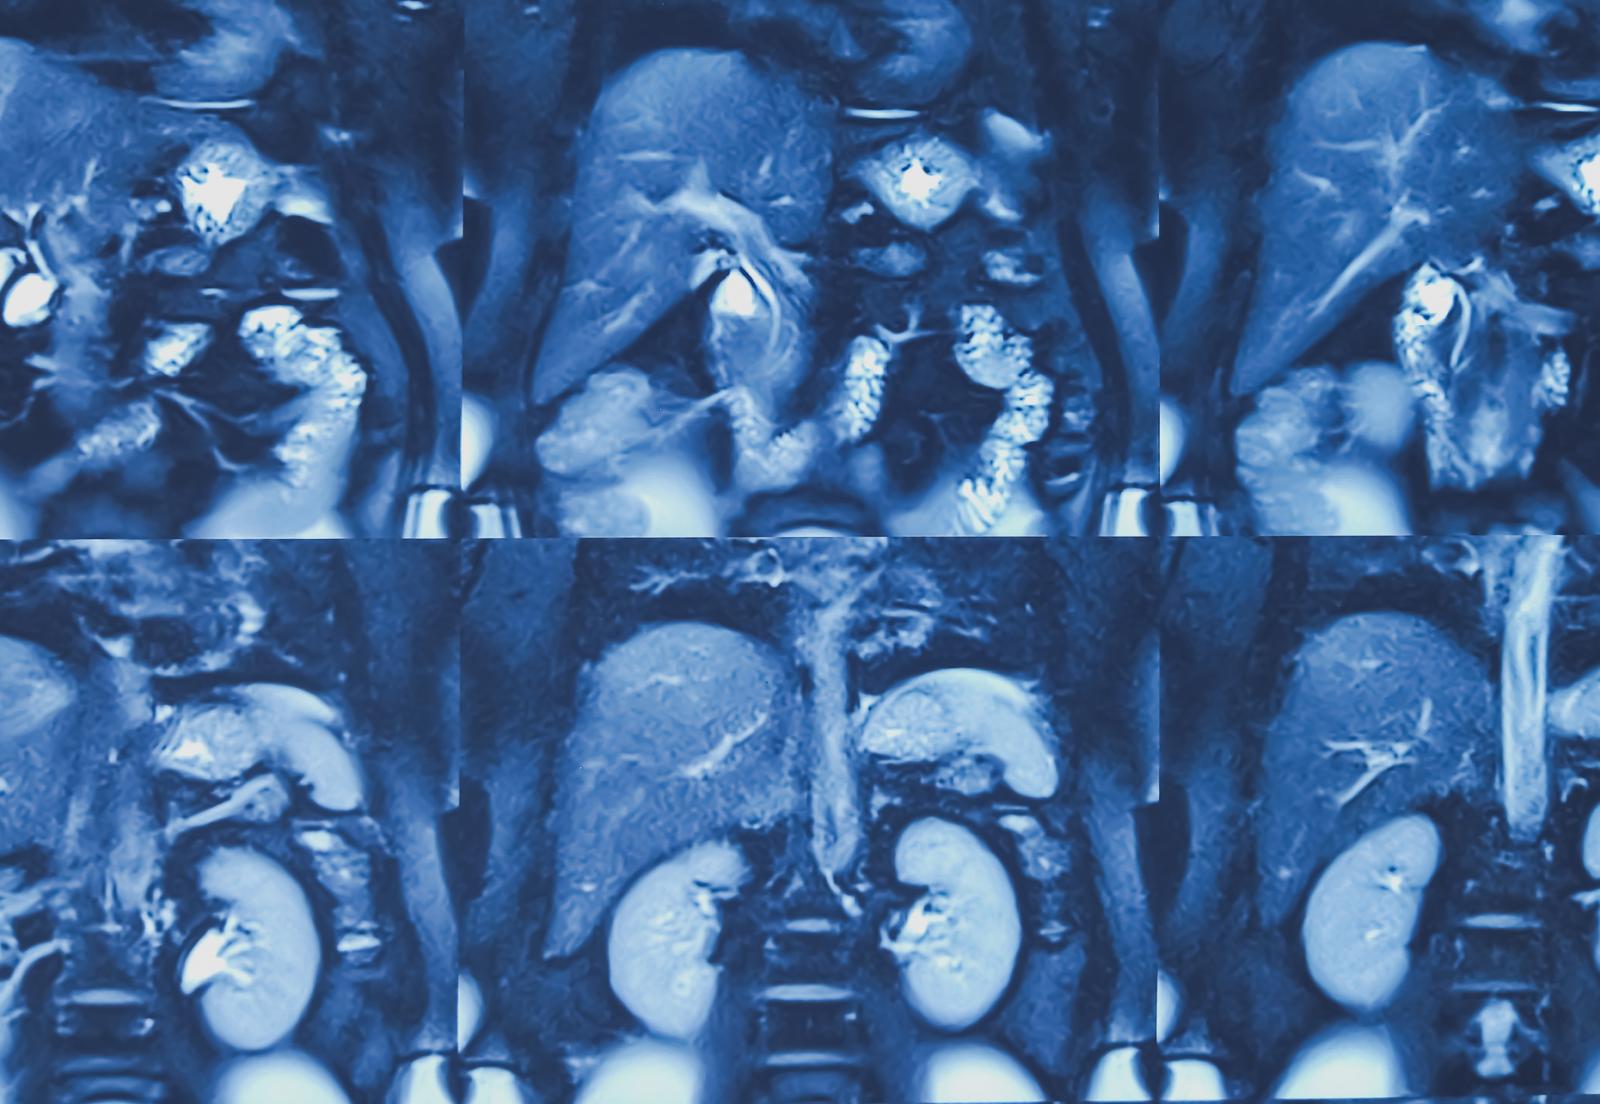

Biliary tract cancers affect parts of the body involved in storing and transporting bile, including the bile ducts and gallbladder. The disease is often diagnosed at a late stage when surgery is no longer possible.

Image credit: iStock